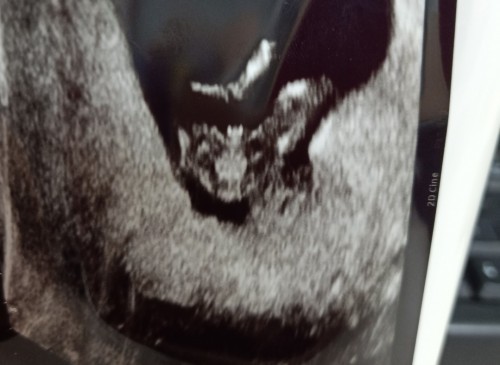

แบบนี้จะเป็นเพศไหนค่ะ 12+5wk

แบบนี้เป็นเพศไหนค่ะ55 อยุครรภ์12+5wk

ขอให้ได้ตามหวังนะคะ